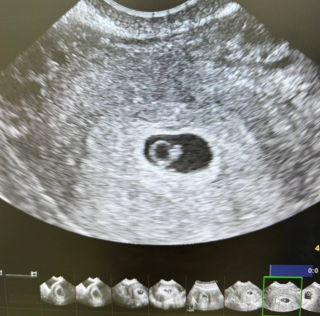

На УЗИ:

• визуализируется эмбрион;

• определяется сердцебиение.

Через две недели — прогрессирующая маточная беременность. Пациентка выписана под наблюдение женской консультации.